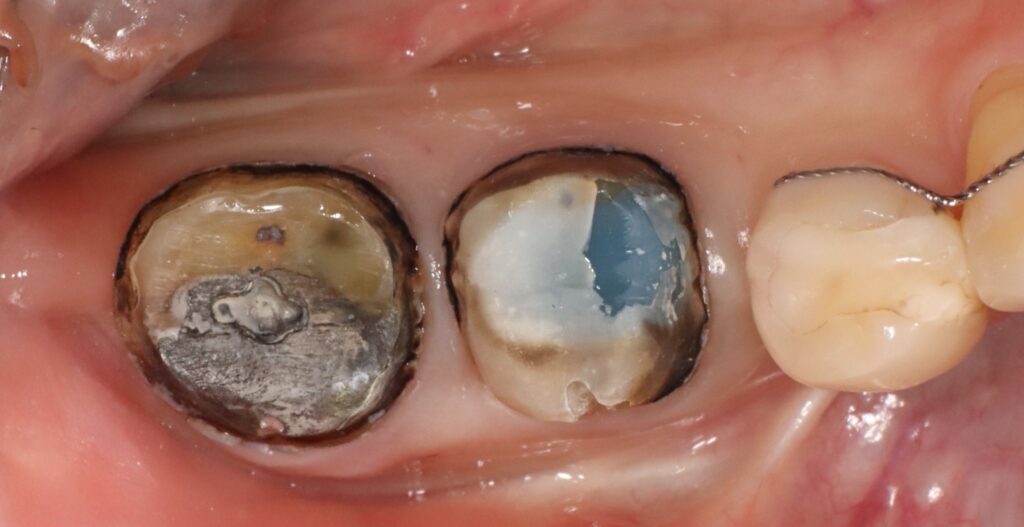

재보철치료는 기존 보철물을 제거하고

새로운 보철로 교체하는 치료로

단순히 외형을 바꾸는 것이 아니라

치아 내부와 잇몸 상태, 교합 관계까지

다시 평가한 뒤 시행하는데요.

오래된 보철물 아래 충치가 생기거나

잇몸이 퇴축되어 경계가 드러난 경우,

접착 불량으로 냄새나 통증이 발생할 때

필요하며 이는 단순한 교체가 아니라

구강 건강을 재정비하는 과정임을

이해하는 것이 중요합니다.

잘 맞지 않았던 기존 보철물을 제거하고

내부의 단단한 재료인 코어부터 제거하여

다시 재충전후 보철을 진행하여 현재까지

통증 없이 현재까지 잘 유지하고 계십니다.